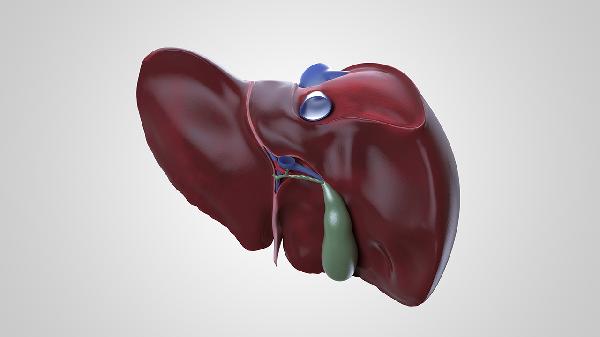

肝脏肿块可能是肝囊肿、肝血管瘤、肝脓肿、肝癌、肝腺瘤等疾病的表现。肝脏肿块通常由感染、遗传、代谢异常等因素引起,建议及时就医明确诊断。

肝囊肿多为先天性或退行性病变,囊内充满液体。可能与胆管发育异常有关,通常表现为右上腹隐痛、饱胀感。无症状小囊肿无须治疗,较大囊肿可考虑超声引导下穿刺抽液或腹腔镜手术。常用药物包括消炎利胆片、熊去氧胆酸胶囊等,需在医生指导下使用。

肝血管瘤是肝脏常见良性肿瘤,可能与雌激素水平或血管发育异常有关。多数无明显症状,较大血管瘤可能导致压迫性疼痛。通常通过超声或CT确诊,直径小于5厘米且无症状者可定期观察,必要时行介入栓塞治疗。

肝脓肿多由细菌或寄生虫感染导致,常伴有发热、寒战、肝区疼痛。可能与胆道感染、败血症有关。治疗需静脉注射抗生素如头孢曲松钠注射液,严重者需穿刺引流。同时需控制糖尿病等基础疾病。

肝癌包括原发性肝癌和转移性肝癌,可能与乙肝病毒感染、肝硬化、黄曲霉毒素暴露有关。典型症状为体重下降、黄疸、腹水。确诊需结合甲胎蛋白检测和增强CT,治疗方式包括手术切除、靶向药物如仑伐替尼胶囊等。

肝腺瘤多见于长期服用避孕药的女性,与激素刺激有关。多数无症状,较大腺瘤可能破裂出血。建议停用相关药物,定期影像学复查。必要时行手术切除,避免活检以防出血。